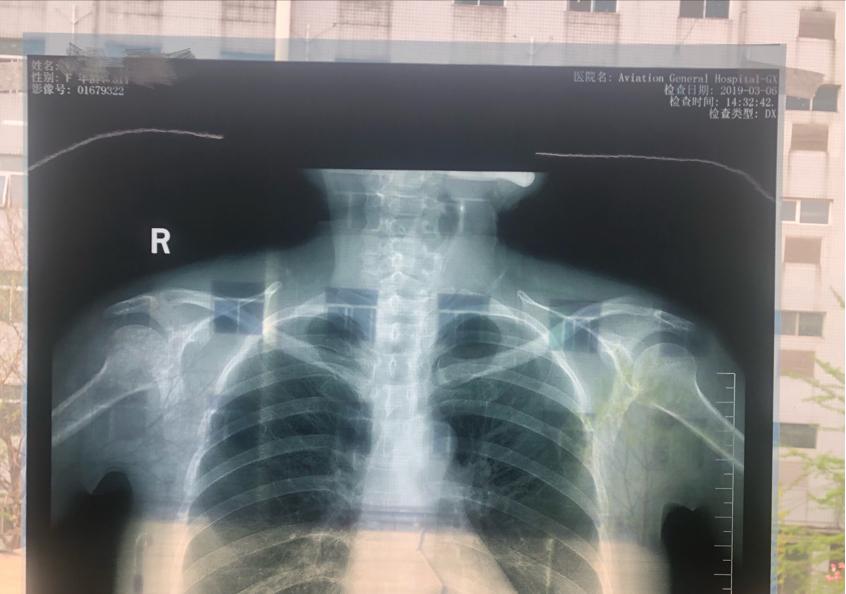

1)片子的图像、文字清晰,没有杂物。片子最好选择纯色背景,要平整没有杂物和杂色,图片摆放要水平没有倾斜,影像学片子上的英文字母和上下左右要清楚。下图中,片子中有楼层的重影,拍摄范围也不完整,不属于一个合格的影像学片子。